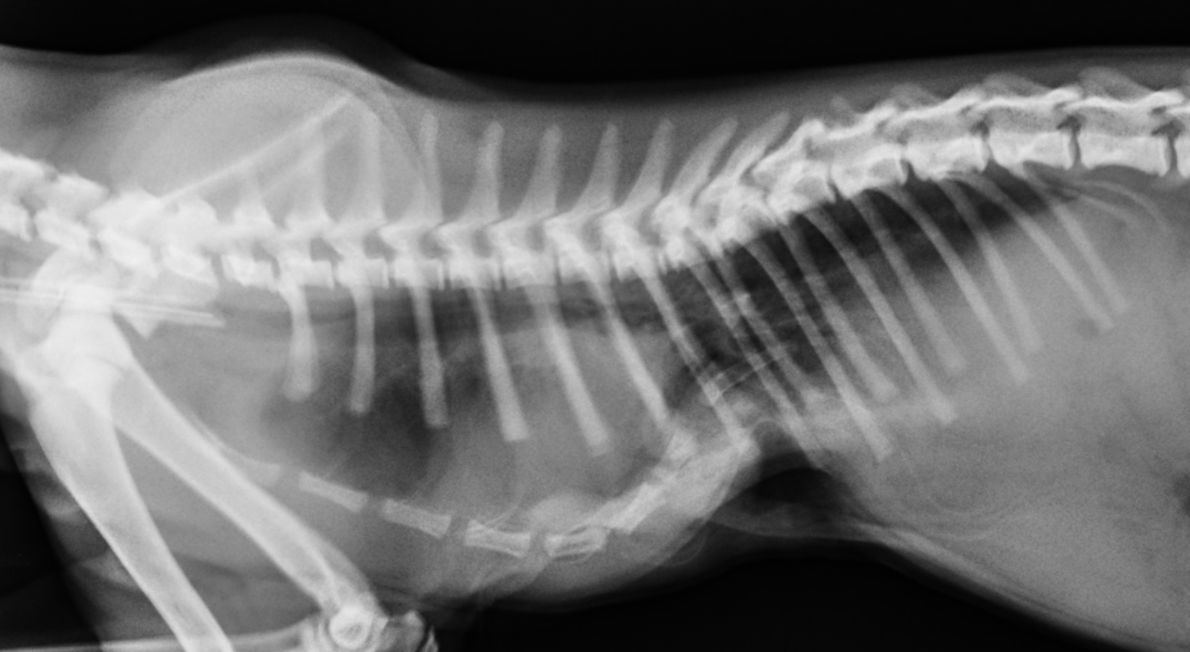

Fracture Salter Harris Type I du fémur distal chez Olaf

Fracture Salter Harris Type I du fémur distal chez Olaf (profil et face)

Fracture Salter Harris Type I du femur distal chez Olaf traitée par un brochage en croix (profil et face)